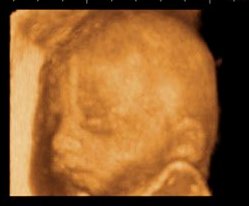

Il bambino ora pesa circa 850 grammi ed è lungo circa 35 centimetri. I nervi del suo sistema uditivo si sviluppano sempre di più e il liquido amniotico che lo circonda veicola i suoni che arrivano dall’esterno fino alle sue orecchie, specialmente quelli del battito del tuo cuore, dello stomaco, dell’intestino e delle voci di mamma e papà. Ora lui può ascoltare tutti questi suoni e li riconoscerà una volta nato. Le palpebre cominciano ad aprirsi, l’iride si caratterizza di quel colore blu tipico dei neonati, il grasso sottocutaneo si accumula sempre di più per la sua termoregolazione e i testicoli, nei maschietti, scendono nello scroto.